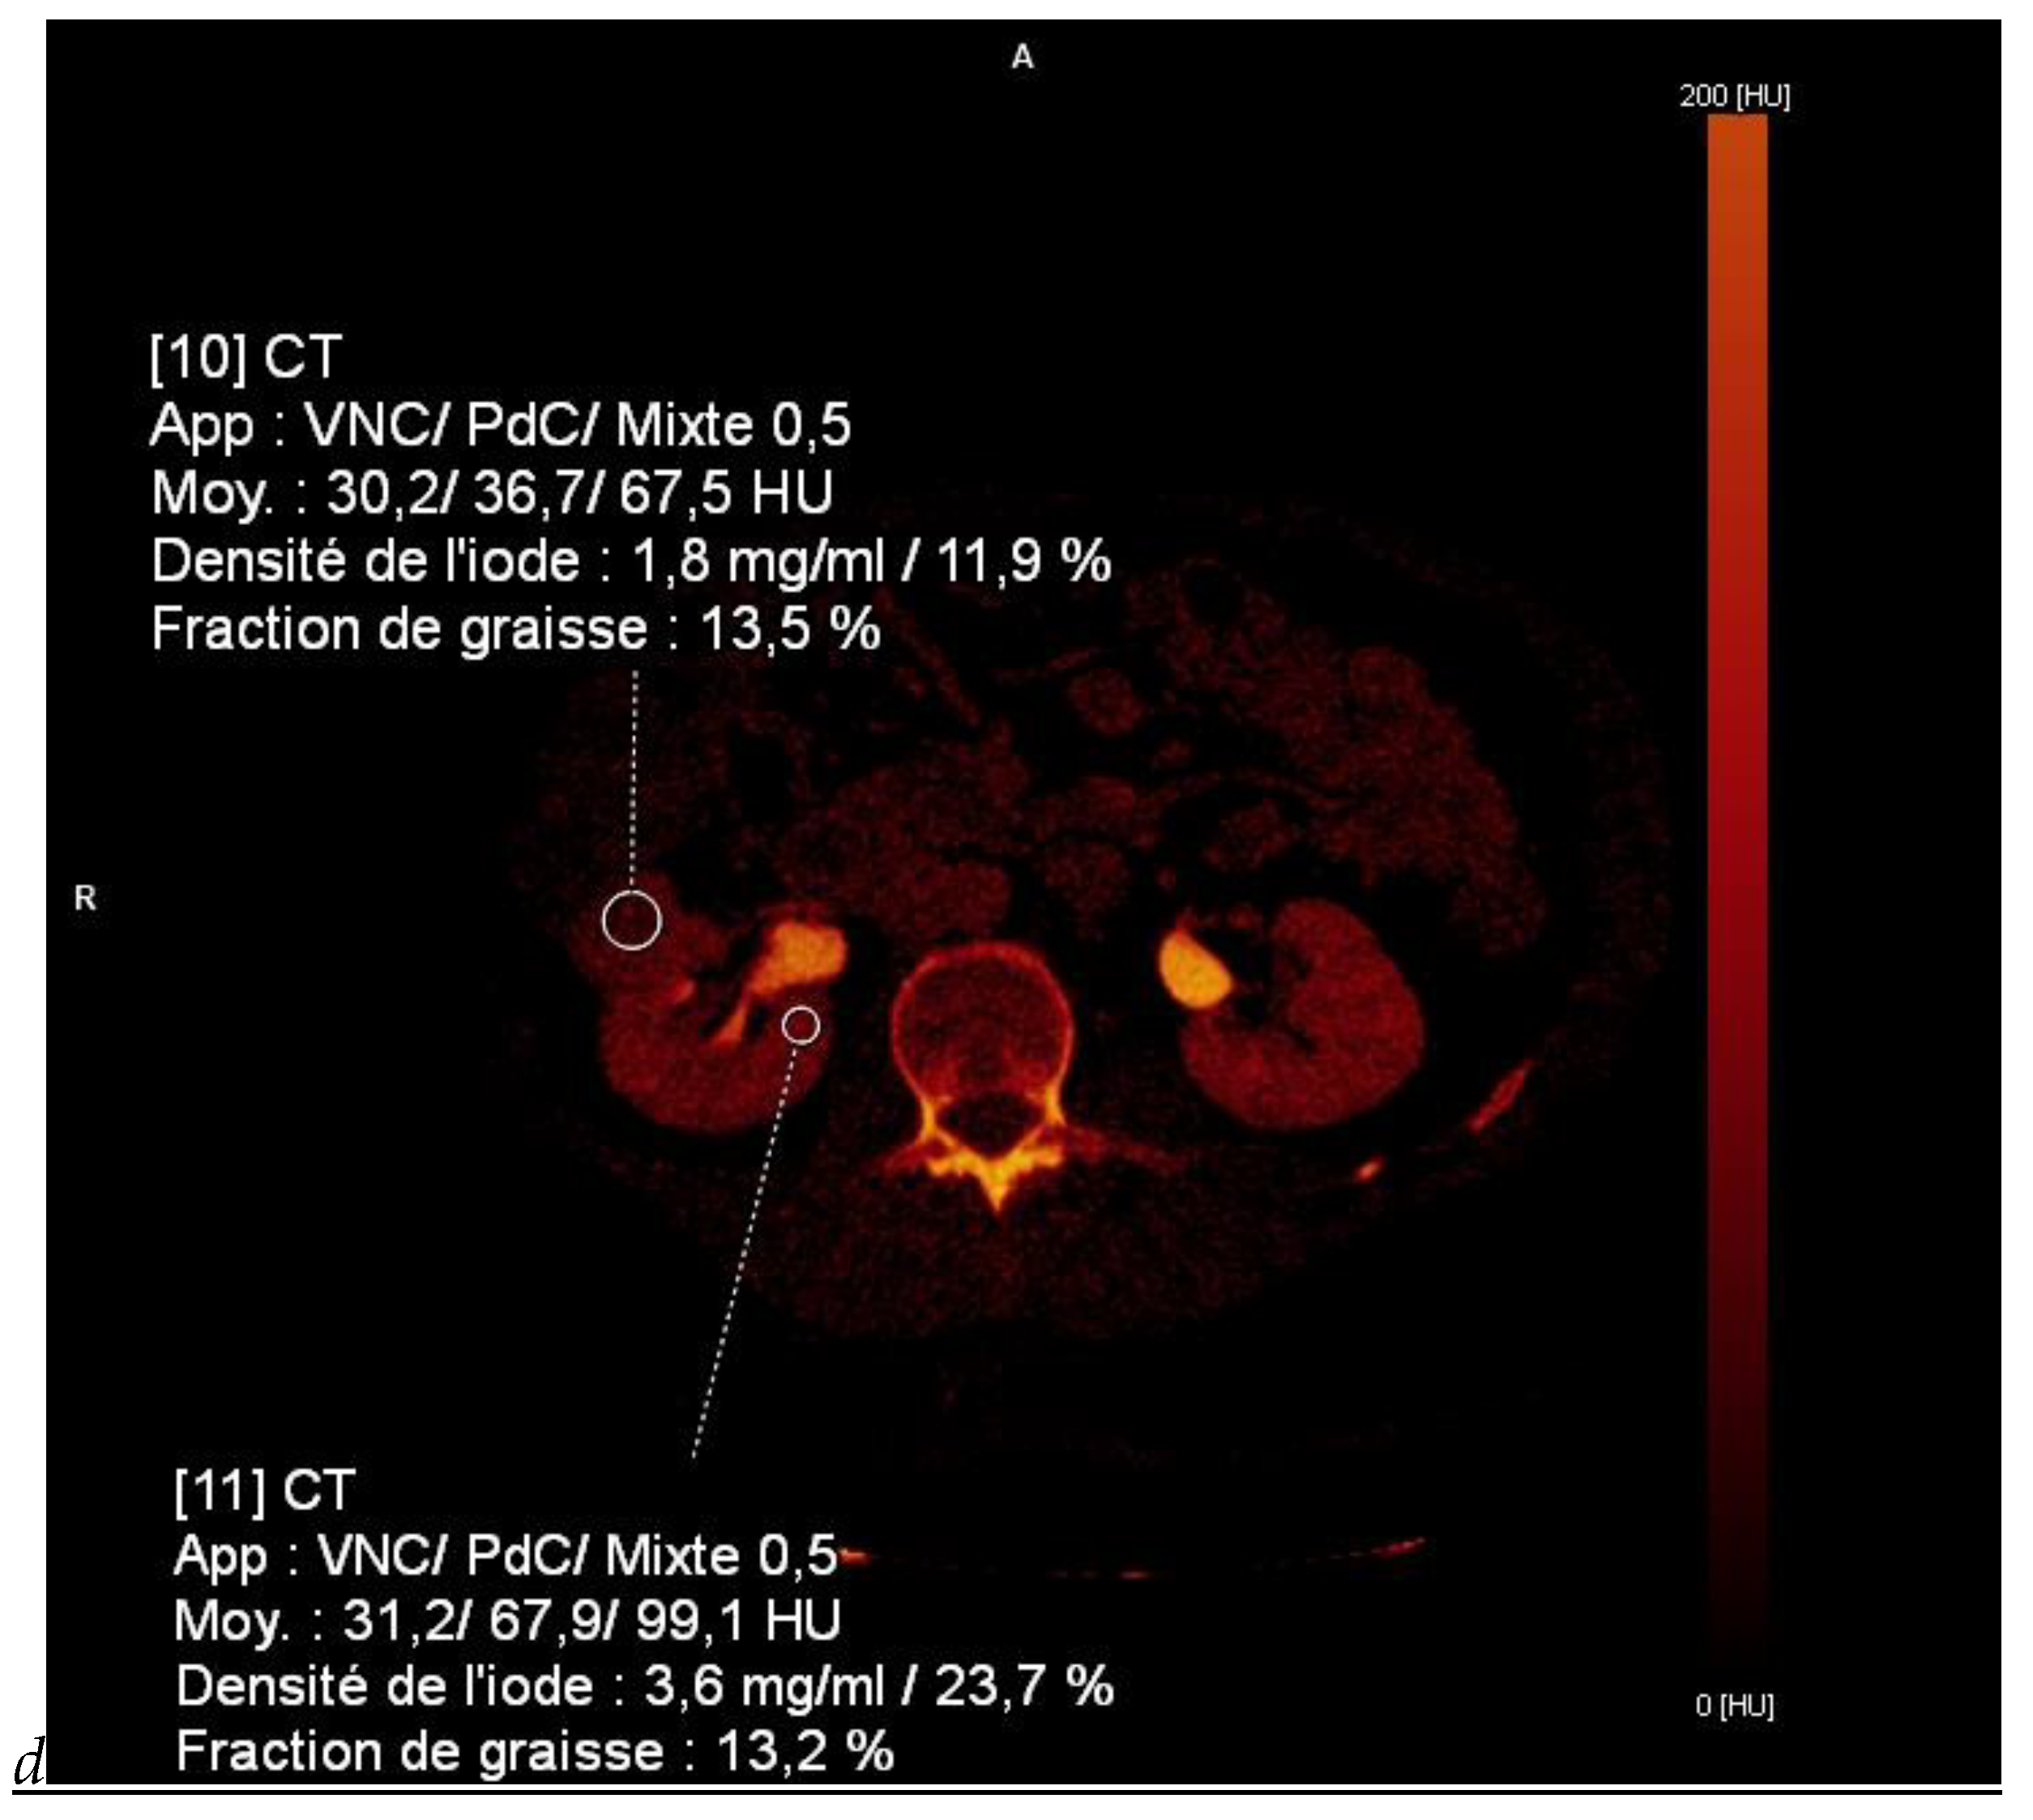

Figure 4.

Multiphasic CT enhancement of a papillary renal cell carcinoma in the middle part of the right kidney of a 63-year-old woman. (A) Mean unenhanced attenuation was 35 HU. (B) Mean corticomedullary phase attenuation was 45 HU. (C) Mean nephrographic phase attenuation was 59 HU. (D) Mean excretory phase attenuation was 65 HU.